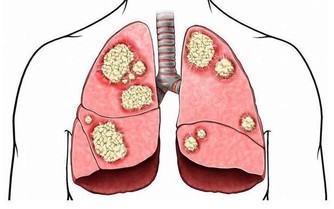

臨床研究發現,人體隨著年齡的增長骨骼中的鈣會隨著流失,從而導致骨質疏鬆等病症,骨質疏鬆為例,50歲以上的發病率為28%,60歲以上的發病率為58%,80歲以上的發病率會高達100%,除了年齡增長必然的鈣質流失外,生活中還有一些飲食上的因素會偷偷的帶走身體中的鈣。所以臨床中有很多案例,吃了將近一年的多的鈣片後去體檢反而骨密度降低了,其實這種情況很有可能是出在了飲食上。那麼究竟是哪些食物能帶走鈣呢?